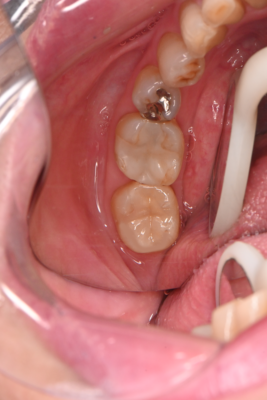

術後↓

見た目だけでなく適合もかなり良いです。

【治療内容】イーマックスインレー